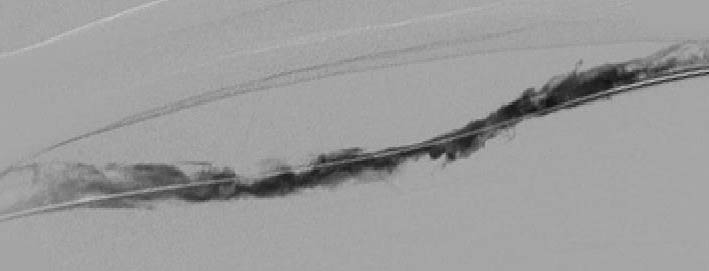

Промежуточный результат катетер-управляемого тромболизиса – появление минимального кровотока в исходно тотально тромбированной поверхностной бедренной вене.

Финальный результат катетер-управляемого тромболизиса – полное восстановление кровотока с растворением всех тромбов в исходно тотально тромбированной поверхностной бедренной вене.